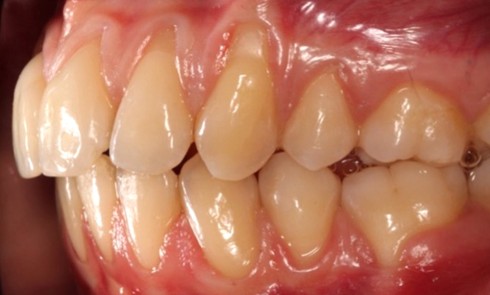

Article réservé à nos abonnés Prise en charge occluso-prothétique des conséquences orales et maxillo-faciales du bruxisme : apport de la prothèse amovible de recouvrement

Le bruxisme est défini comme le grincement parafonctionnel des dents, ou encore comme une habitude orale composée de tapotements, de...